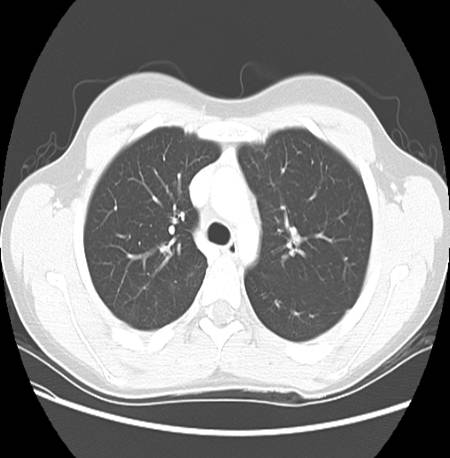

A CT chest was also ordered to further characterize the pulmonary involvement.

Describe chest CT.